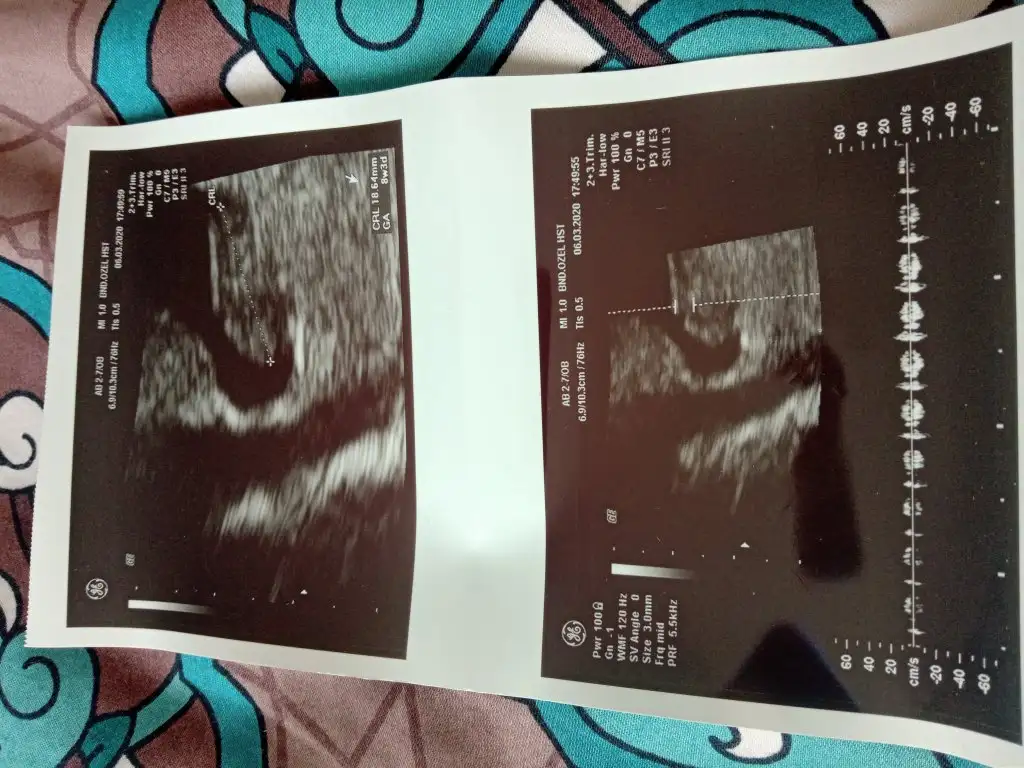

Arkadaşlar 3kizim var bu 4. Hamileliğim Rabbim nasip ederse gönlümüzde erkek var lütfen tahmin edermisiniz kesem neye benziyor...

8+3 bize de tahminde bulunabilir misiniz 🥰 çok merak ediyorum 💙

Eklentiler

• IMG_20200306_134531_3.webp

IMG_20200306_134531_3.webp

65 KB · Görüntüleme: 76